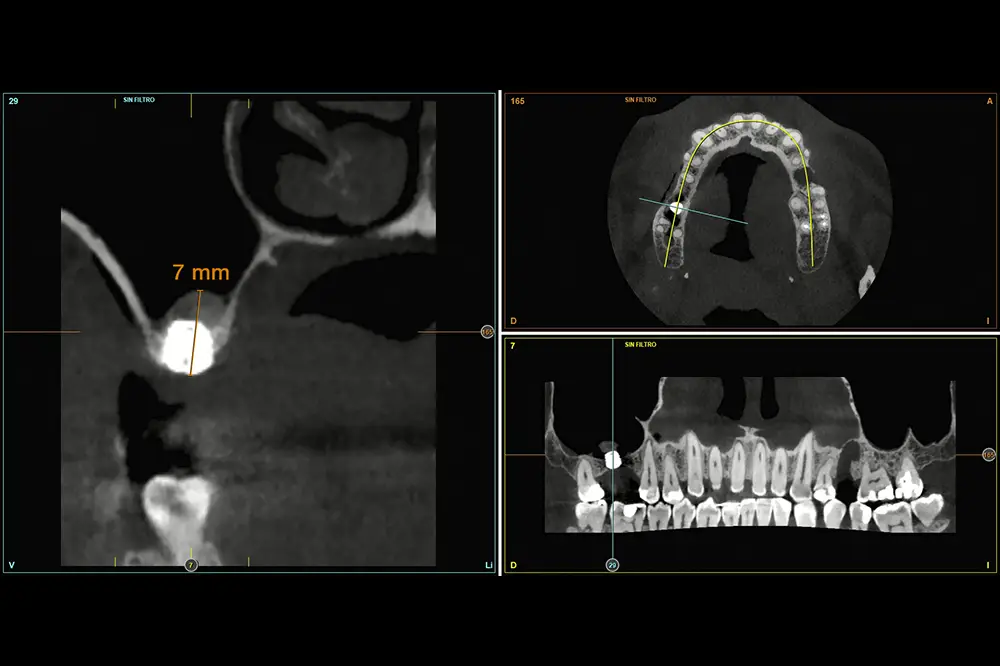

En este caso, la paciente acude con la exodoncia realizada hace dos años de la pieza 16 y una gran atrofia vertical, existiendo únicamente 1 mm en algunas zonas de la cresta, como el área más vestibular, y hasta 3 en la zona más palatina (fig. 9). Procedemos a la realización del fresado tal como se ha descrito en el caso anterior y colocamos el mismo tipo de injerto (autólogo y PRGF- Endoret) y un implante de 4,5 mm de longitud (fig. 10 y 11). Tras la cicatrización a los 4 meses, observamos el aspecto de la zona de la colocación del implante, donde tenemos ahora una altura de 7 mm (fig. 12).

Llegados a este punto, se retira el implante de 4,5 mm al igual que en el caso anterior, de forma totalmente atraumática, y se coloca un implante de 6,5 mm de longitud (fig. 13). Se realiza la carga del implante a los 4 meses y tras 3 años de seguimiento comprobamos la estabilidad total del tratamiento realizado (fig. 14).

Fig. 12. Estado de la zona una vez consolidado el injerto a los 4 meses.

Fig. 13. Colocación del implante de 6,5 mm de longitud tras el recambio del implante de 4,5 mm.